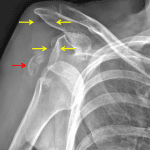

- Anterior shoulder dislocation

- Acute comminuted fracture of the greater tuberosity with 2 cm superolateral displacement

- Fat-fluid levels overlying the acromion and coracoid process

- Mild degenerative changes of the acromioclavicular joint

- Anterior shoulder dislocation

- Greater tuberosity fracture

Anterior shoulder dislocation. Acromioclavicular joint alignment is maintained.

Acute comminuted fracture of the greater tuberosity with 2 cm superolateral displacement.

Fat-fluid levels overlying the acromion and coracoid process consistent with lipohemarthrosis.

Mild degenerative changes of the acromioclavicular joint.